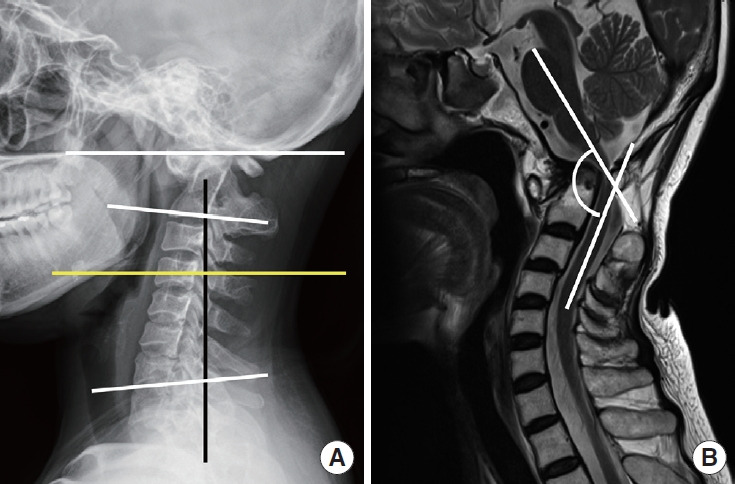

Methods: A retrospective analysis was performed on 28 patients who underwent craniocervical realignment between 2014 and 2022 for CVJ kyphosis with accompanying negative sagittal imbalance. Clinical outcomes were evaluated using the Neck Disability Index (NDI), visual analogue scale for neck pain, and the Japanese Orthopaedic Association (JOA) score. Radiographic parameters included the C0-2 angle and the C2-7 sagittal vertical axis (SVA). Favorable outcomes were defined as an improvement of more than 20 points in the NDI and a JOA recovery rate exceeding 50%. Multiple linear regression and receiver operating characteristic (ROC) curve analyses were conducted to identify independent predictors and to determine optimal threshold values.

Results: Significant improvements in both clinical outcomes and radiographic alignment were observed in association with craniocervical realignment surgery. Patients who achieved favorable outcomes exhibited greater postoperative changes in the C0-2 angle and the C2-7 SVA. Multivariate analysis identified changesm in the C0-2 angle (p=0.019) and C2-7 SVA (p=0.010) as independent predictors of NDI improvement, while age (p=0.033) and C2-7 SVA change (p=0.037) were independently associated with the JOA recovery rate. ROC curve analysis determined optimal cutoff values of ≥10.65° for C0-2 angle change and ≥19.2 mm for C2-7 SVA change, with corresponding area under the curve values of 0.872 and 0.802, respectively.